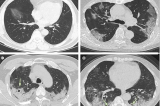

Trung Quốc: Nhiều người bị “phổi trắng”, nghi xuất hiện chủng đột biến mới

Trung Quốc Đại Lục bùng phát dịch, người dân liên tiếp đăng ảnh bản thân hoặc người thân bị phổi trắng do nhiễm virus corona mới.